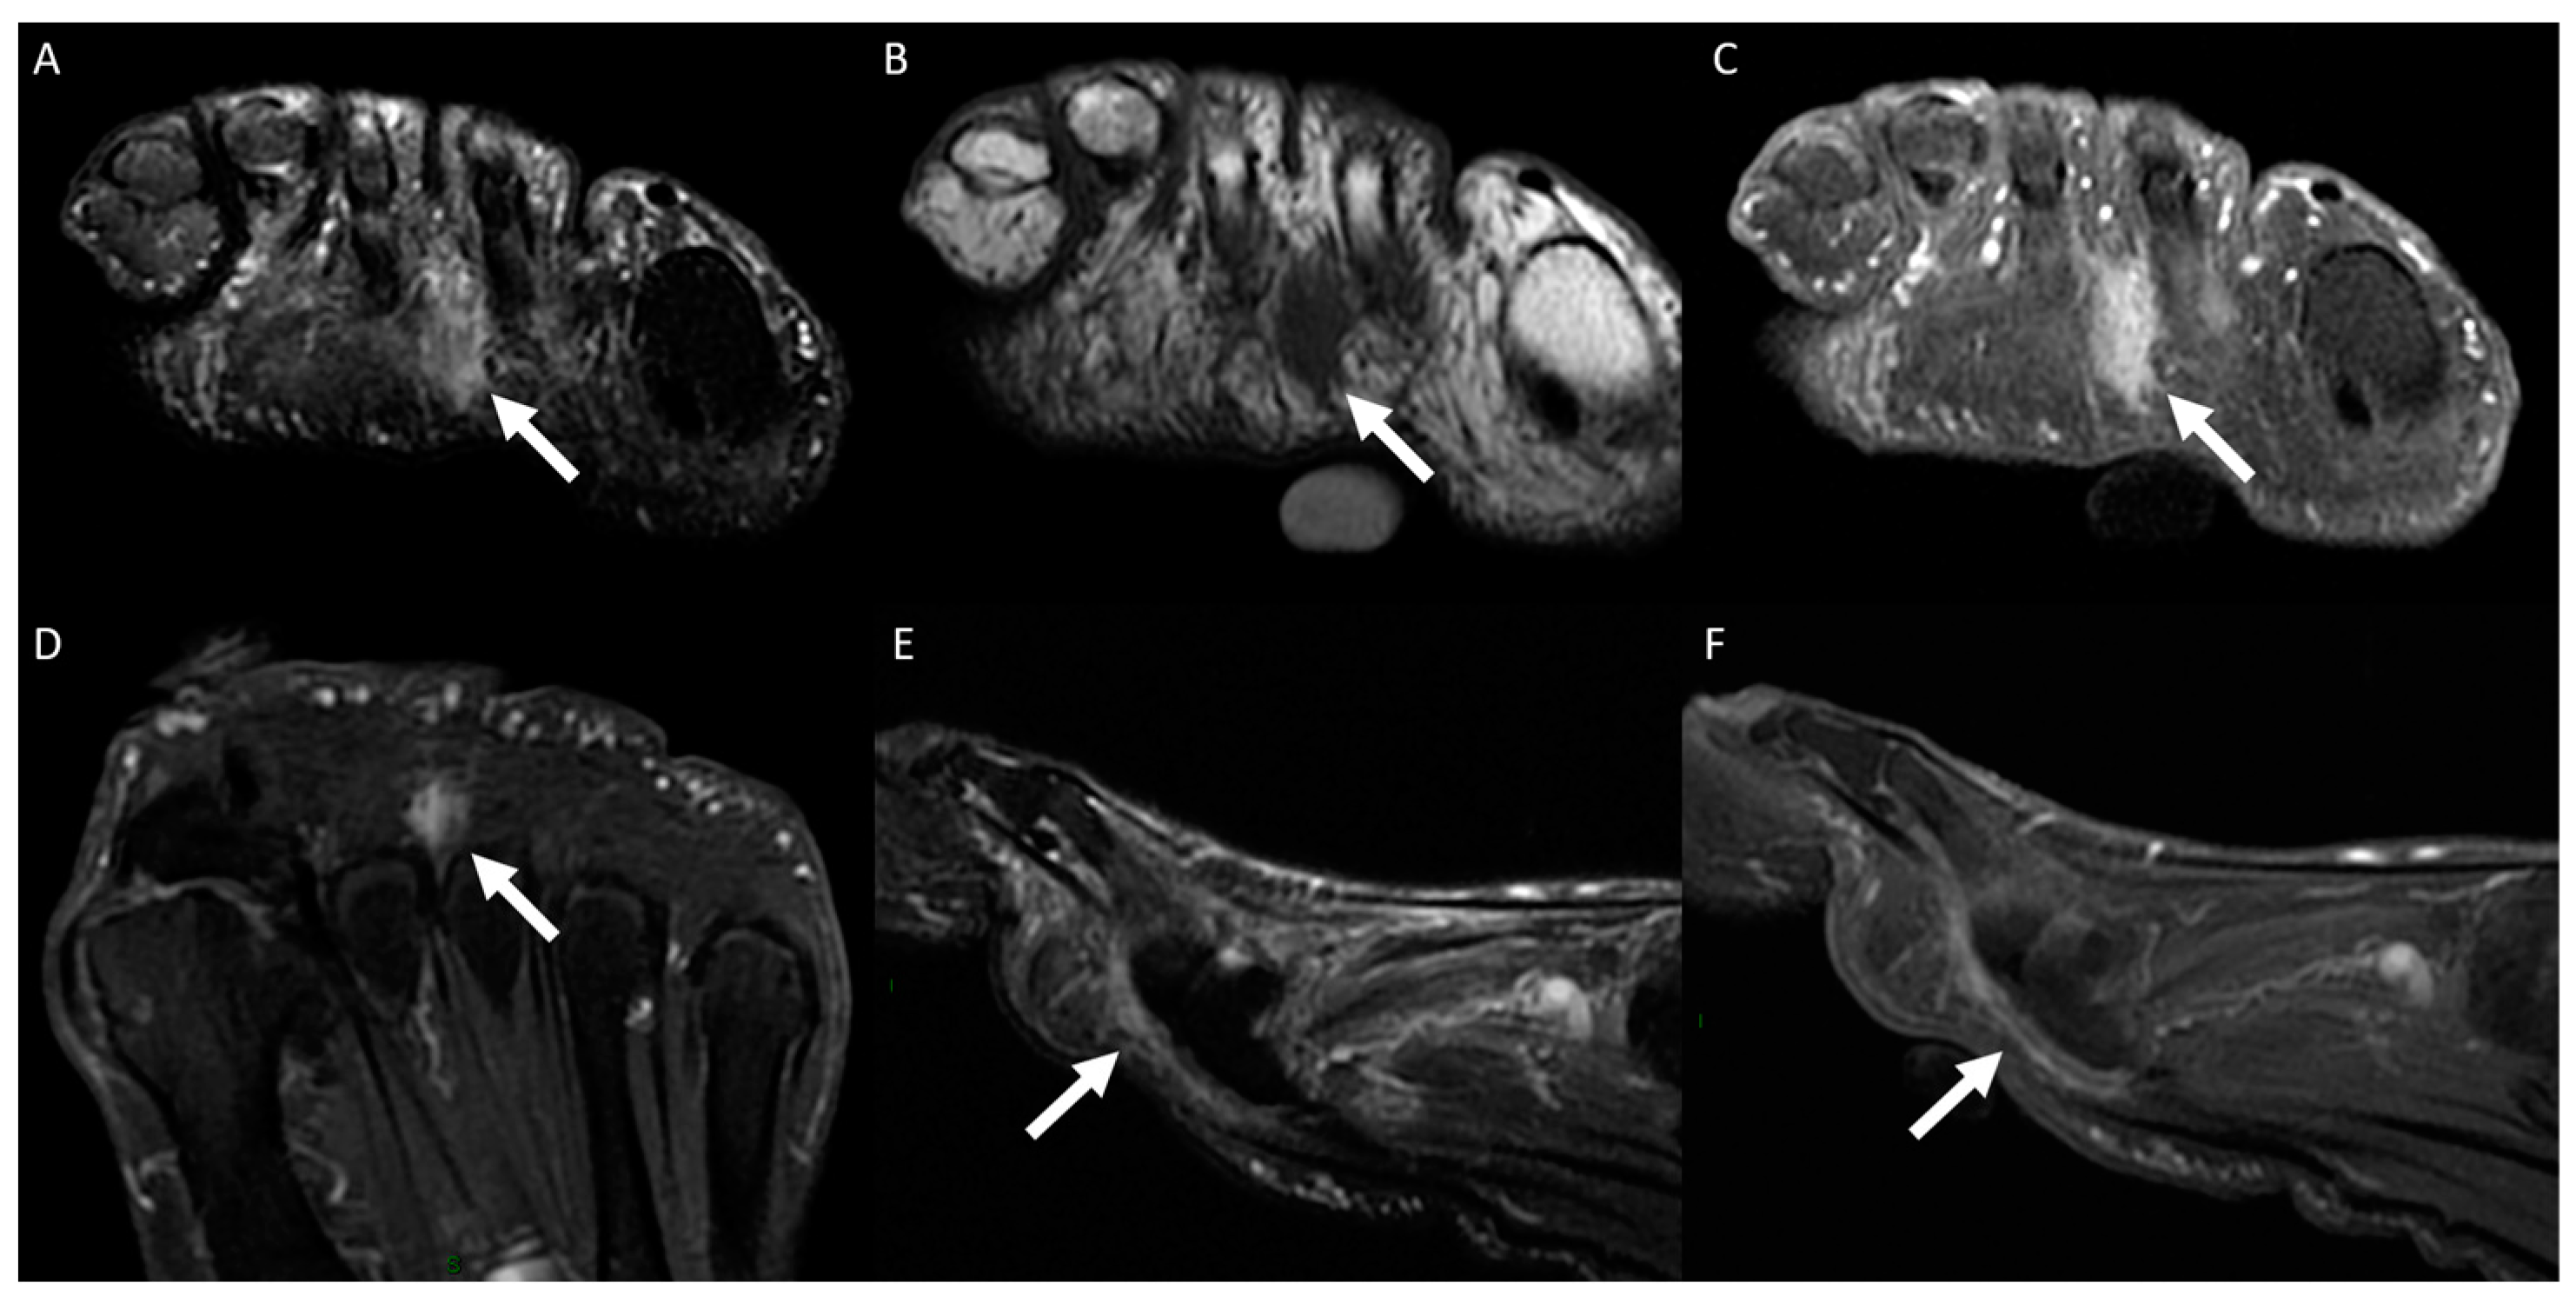

3.2. Distribution of MRI Findings